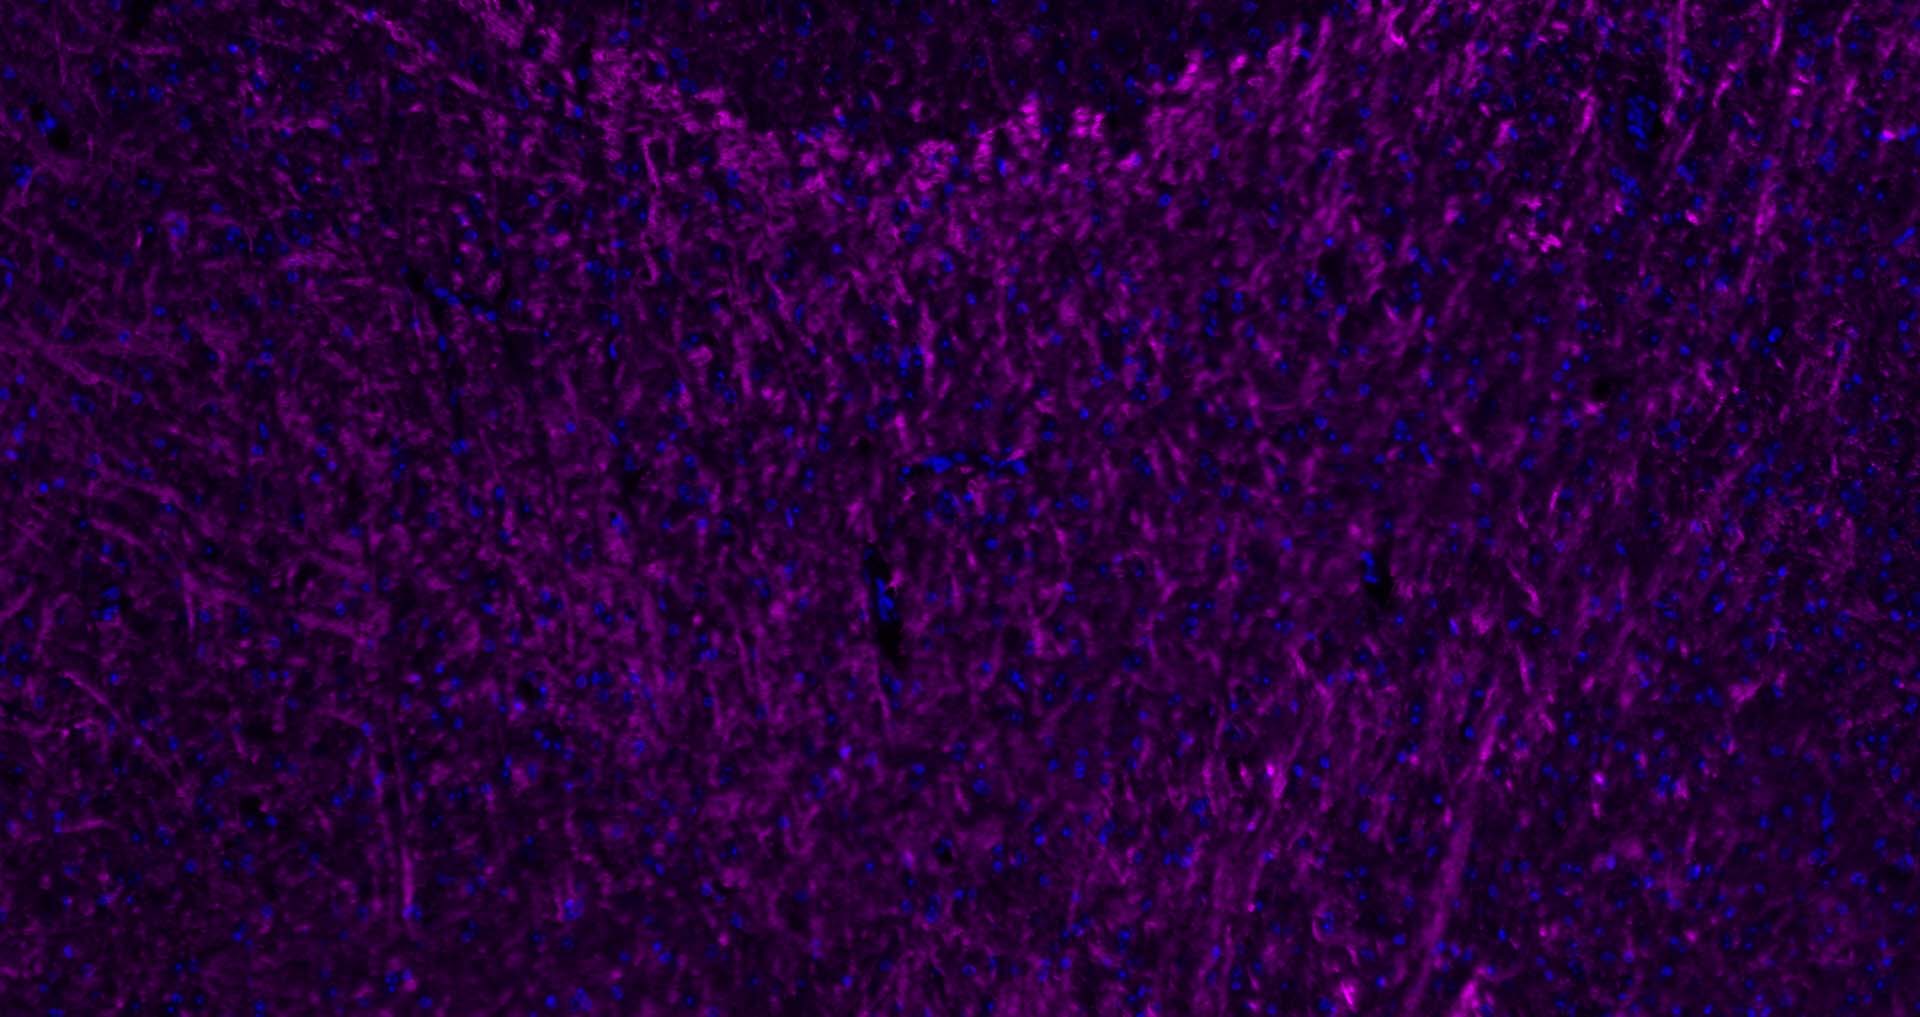

The protein encoded by the classic MBP gene is a major constituent of the myelin sheath of oligodendrocytes and Schwann cells in the nervous system. However, MBP-related transcripts are also present in the bone marrow and the immune system. These mRNAs arise from the long MBP gene (otherwise called "Golli-MBP") that contains 3 additional exons located upstream of the classic MBP exons. Alternative splicing from the Golli and the MBP transcription start sites gives rise to 2 sets of MBP-related transcripts and gene products. The Golli mRNAs contain 3 exons unique to Golli-MBP, spliced in-frame to 1 or more MBP exons. They encode hybrid proteins that have N-terminal Golli aa sequence linked to MBP aa sequence. The second family of transcripts contain only MBP exons and produce the well characterized myelin basic proteins. This complex gene structure is conserved among species suggesting that the MBP transcription unit is an integral part of the Golli transcription unit and that this arrangement is important for the function and/or regulation of these genes.

| 应用 | 已检合格种属 | 预测种属 | 推荐稀释比例 |

|---|---|---|---|

| WB | Mouse, Rat | Human, Rabbit, Pig, Sheep, Cow, Dog, Horse | 1:1000-5000 |

| IHC-P | Human, Mouse, Rat | Rabbit, Pig, Sheep, Cow, Dog, Horse | 1:500-2000 |

| IHC-F | Human, Mouse, Rat | Rabbit, Pig, Sheep, Cow, Dog, Horse | 1:500-2000 |

| IF | Human, Mouse, Rat | Rabbit, Pig, Sheep, Cow, Dog, Horse | 1:500-2000 |

| Flow-Cyt | Rat | Human, Mouse, Rabbit, Pig, Sheep, Cow, Dog, Horse | 1:100-200 |

交叉反应: Human, Mouse, Rat (predicted: Rabbit, Pig, Sheep, Cow, Dog, Horse)